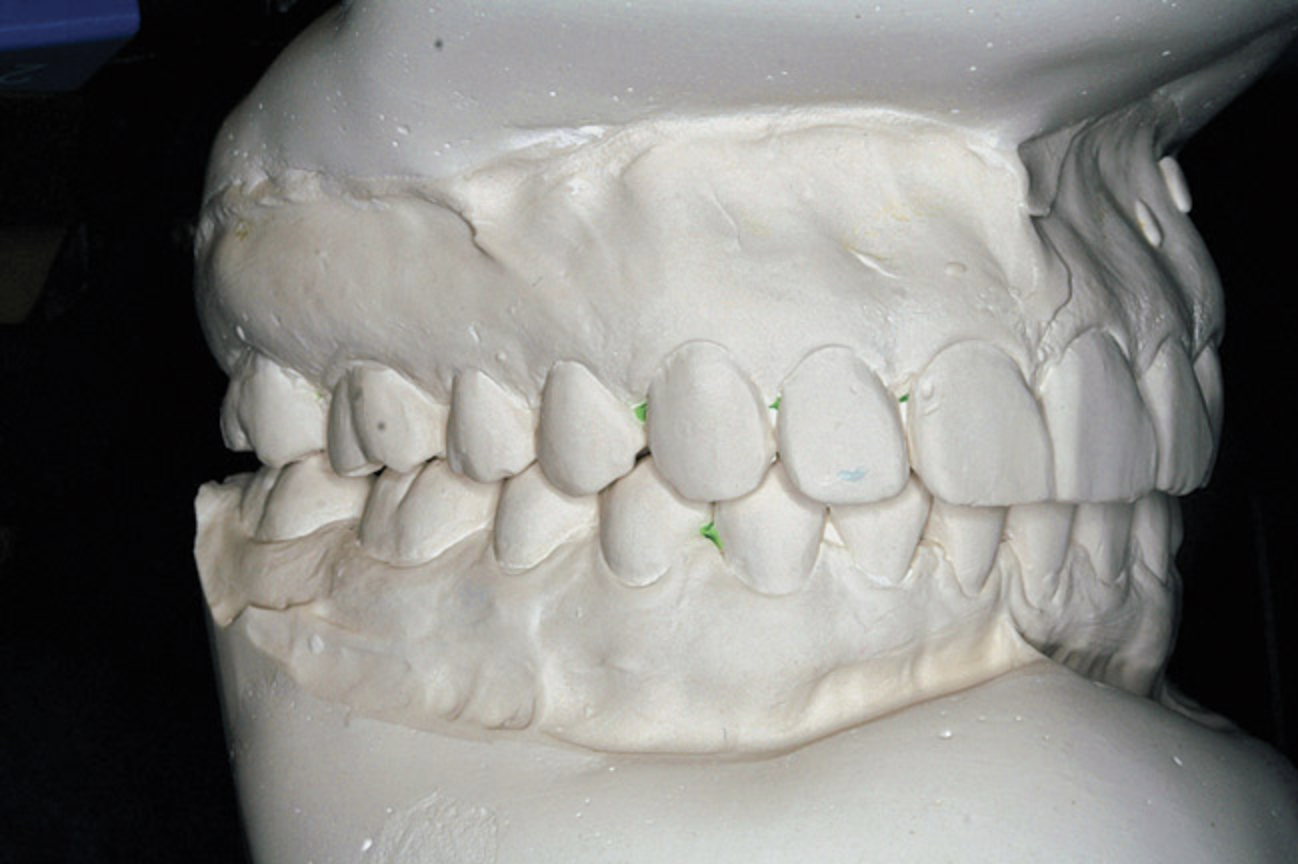

Figure 3  There is a mesial inclination of the maxillary teeth from gingival to occlusal in the esthetic dentition. Maxillary posterior teeth have an axial inclination which converges from the gingival through the occlusal toward a central fulcrum.

Figure 3

All teeth have a characteristic axial alignment that creates esthetic balance. The restorative dentist can alter the appearance of the inclination by reshaping the tooth or with a restoration (Figure 3). However, orthodontic tooth movement can make significant improvements in axial position on a routine basis. The orthodontist should always attempt to set the alignment to the best advantage for the restorative dentist.

While most orthodontists appreciate anterior dental esthetics, some do not consider that the posterior teeth also have a normal alignment angle. The posterior teeth axial line angles appear to converge from the gingival through the occlusal toward a “central fulcrum.7 Alignment of teeth with significant crowding without extractions may cause a flaring of the axial alignment of both anterior and posterior teeth. If orthodontists do not extract teeth or reduce the width of teeth with interproximal reduction when the dental arch perimeter is greater than the skeletal arch perimeter, the teeth will be tipped, creating a “flared” appearance. Tipped teeth are not only esthetically unappealing, they are not centered in bone and do not allow occlusal forces to be directed down the long axis of the root, which impairs long-term stability (Figure 4). If treatment goals cannot be reached without extractions, then extractions must be considered.